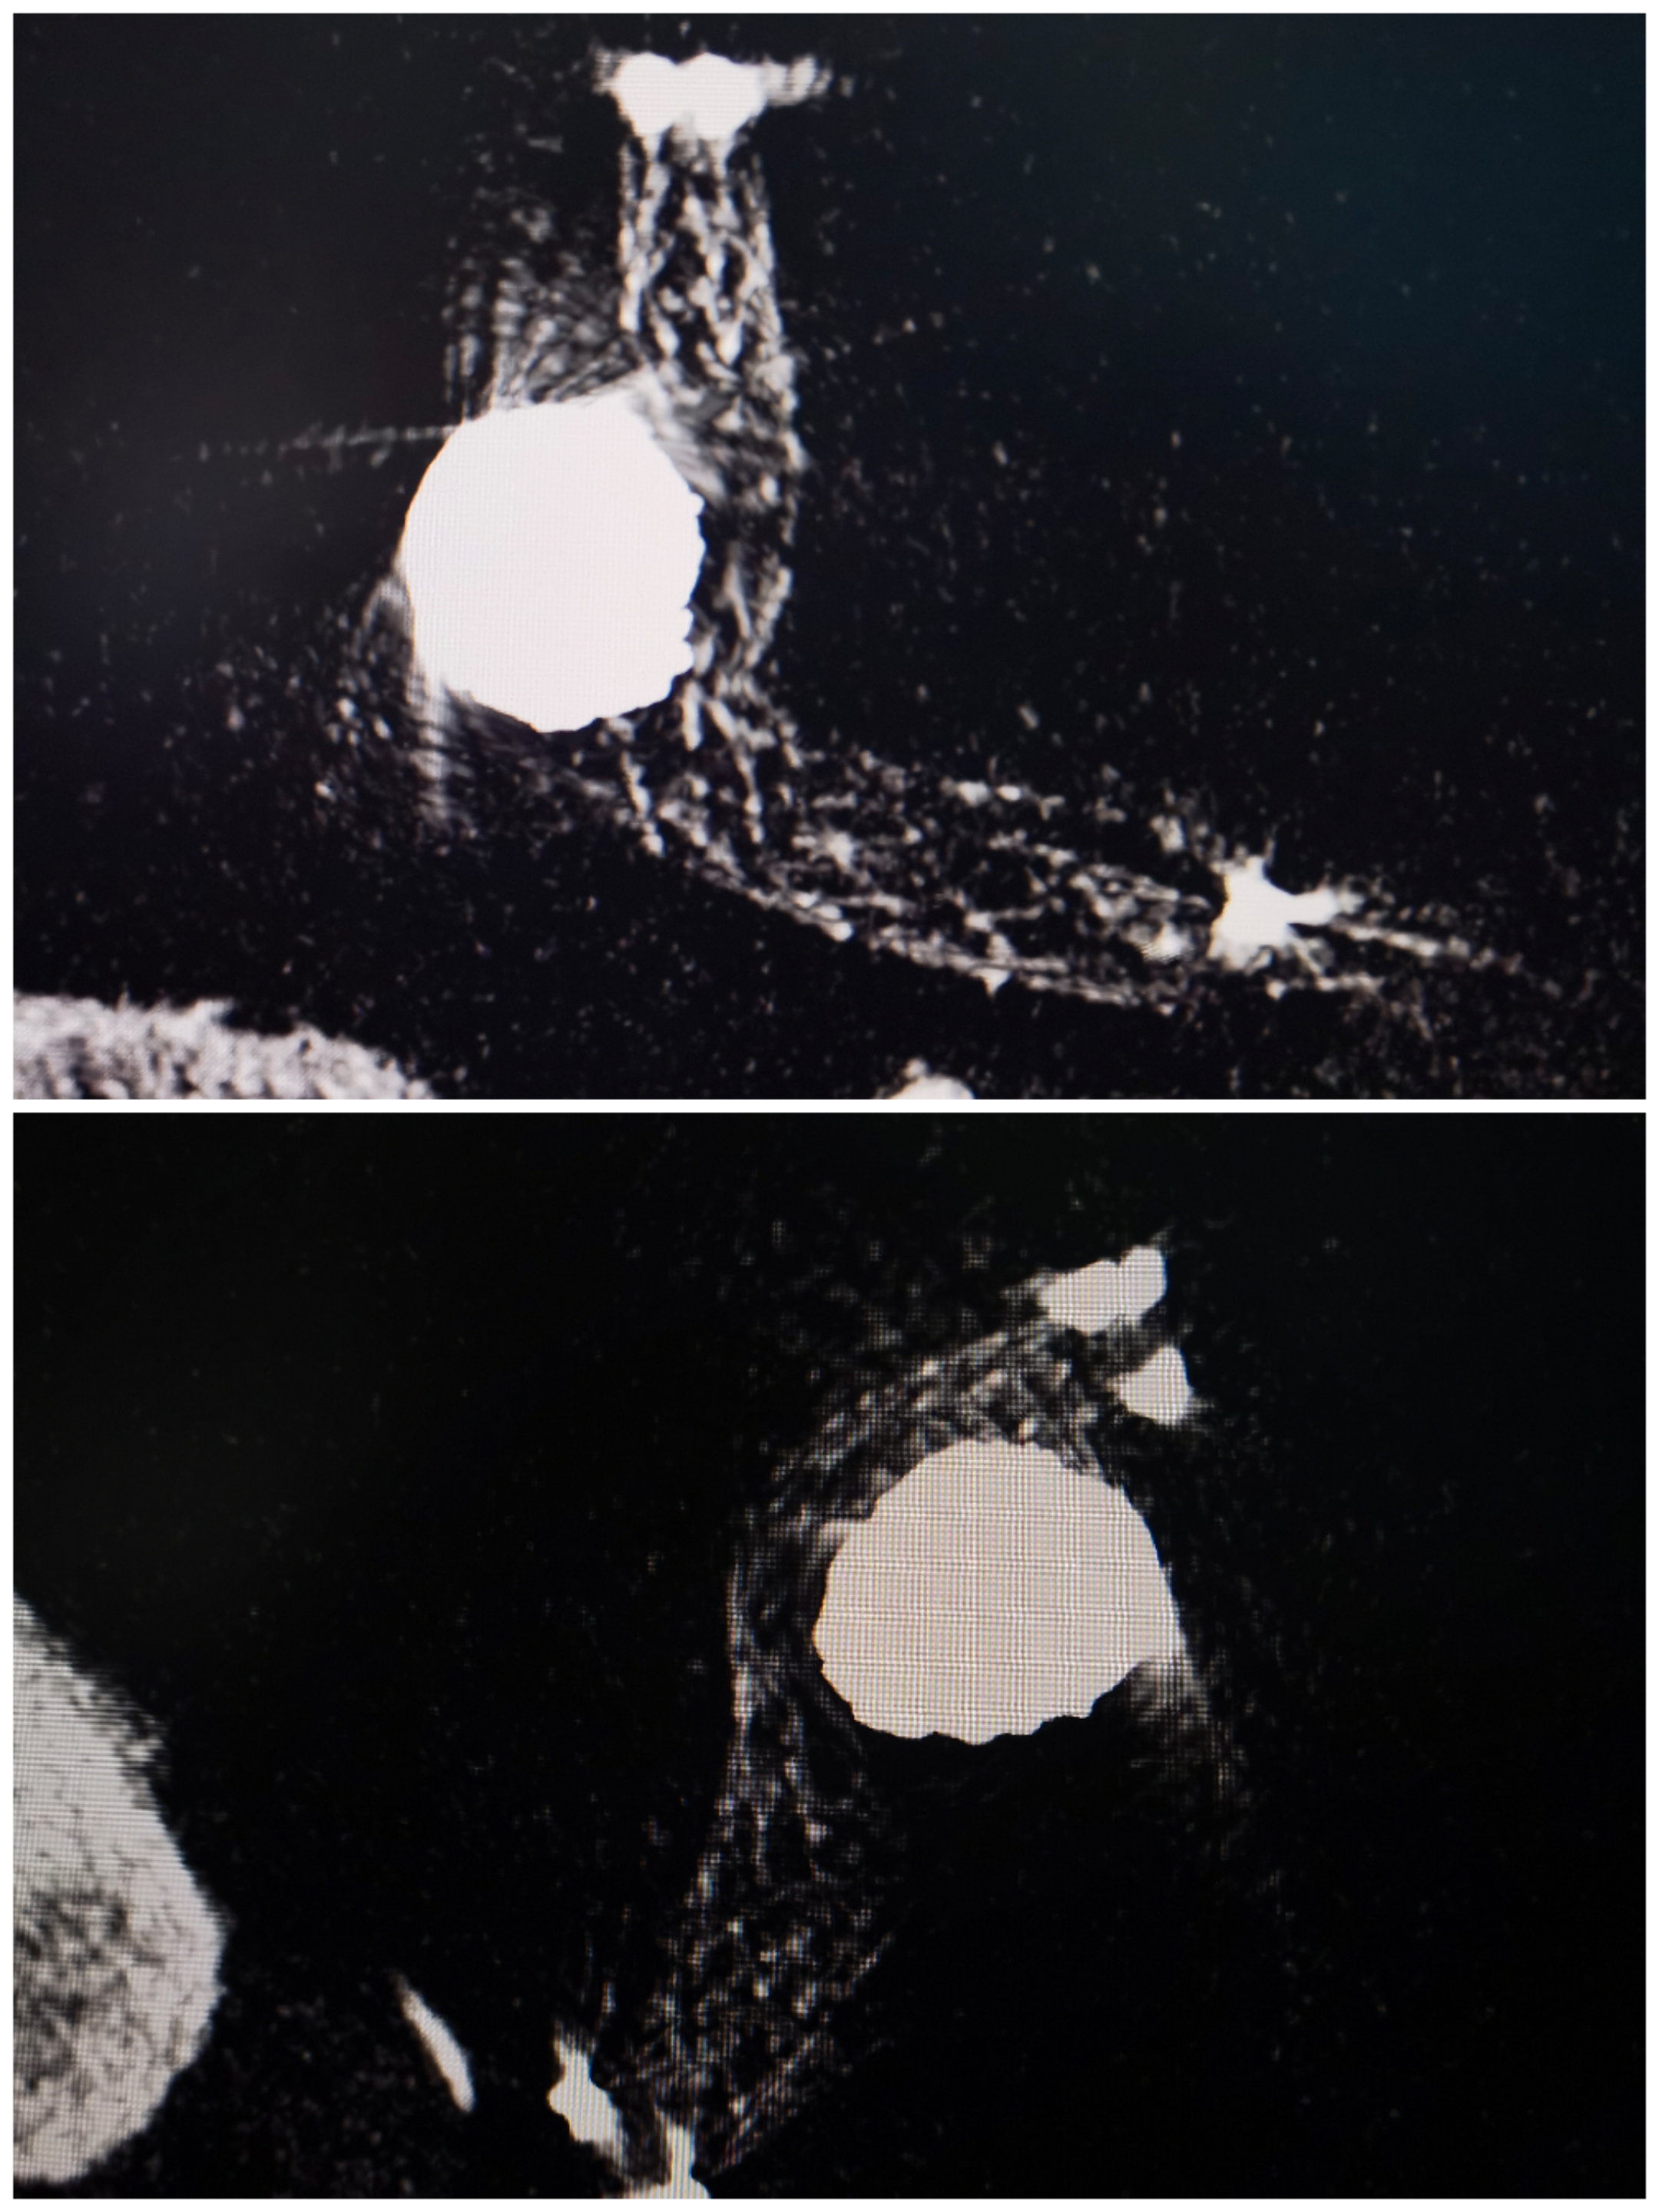

头颅CT情况:SAH

CTA提示前交通动脉瘤,双侧A1发达,似乎是宽颈的

3D重建情况

术后3D重建